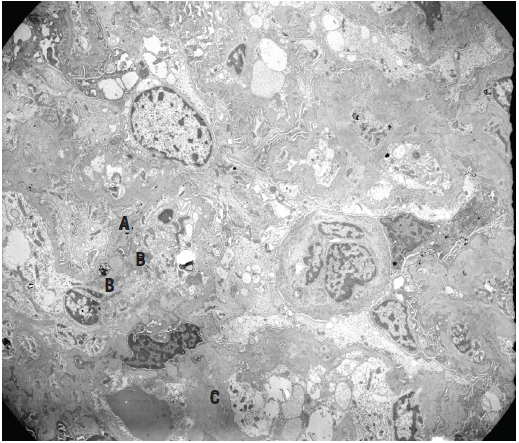

Figure 6. Electron micrograph of a glomerular tuft showing irregularly thickened peripheral capillary basement membranes with scattered subepithelial (A), subendothelial (B), and intramembranous dense deposits, as well as abundant mesangial and paramesangial deposits (C), corresponding to IgA deposition.